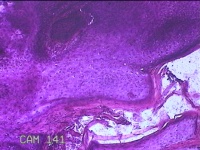

额部肿物

性别

女

年龄

32岁

临床诊断

寻常疣

一般病史

额部起疹1年,不痒。

标本名称

大体所见

灰白暗红色肿物0.7x0.5x0.2cm一个,表面光滑,切开肿物呈实性,切面灰白粉红色,质软。

图4